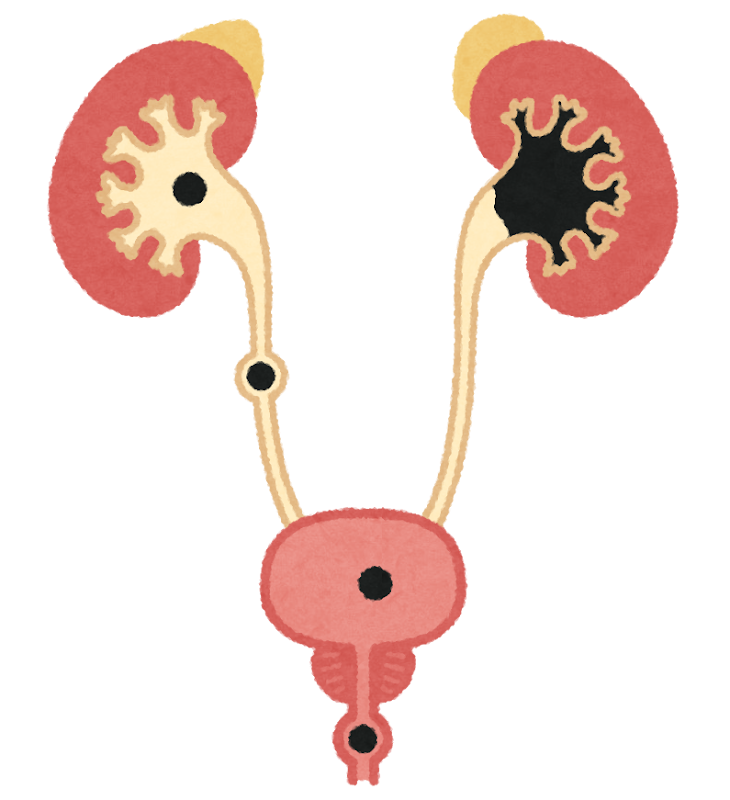

超音波検査

腎臓の大きさや形、構造の変化を確認し、結石や腫瘍、尿管の異常など、原因となる病気がないかを調べます。

腎臓の超音波検査では、次のような異常が見つかることがあります。

- 腎結石・尿管結石

→ 尿の流れが悪くなり、腎機能低下の原因になることがあります。 - 腎臓腫瘍

→ 腎臓の形がいびつになったり、しこりとして確認されます。 - 嚢胞腎

→ 腎臓の中に液体のたまった袋状構造が見つかります。 - 腎盂腎炎

→ 腎盂の拡張や腎臓内部の構造変化がみられます。 - 腎萎縮・腎腫大

→ 慢性腎臓病や炎症などを疑う所見です。

超音波検査は、原因の特定や病状の把握に役立つ検査です。

病気の進み方を予測したり、治療計画を立てるうえで、非常に重要な役割を果たします。